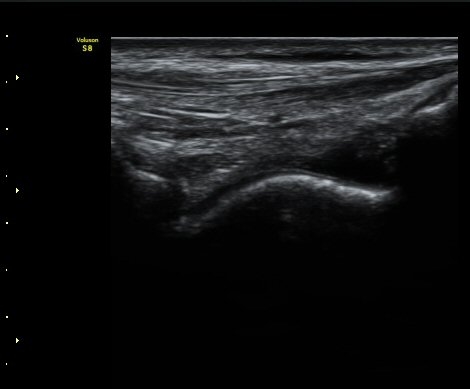

¹ß¸ñ°üÀý ¾Õ Á¾´Ü¸é°Ë»ç¿¡¼­ ¼Ò·®ÀÇ ¼ö¾×Àú·ù°¡ °üÂûµÈ´Ù(±×¸² 1, 2).